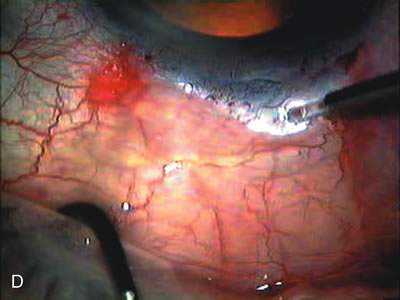

Fig. 3. Partial bleb failure following clear corneal phacoemulsification with foldable IOL. A. Preoperative bleb appearance prior to temporal lens extraction. Preoperative IOP was 12 mm Hg on no antiglaucoma medications. Time from 5-FU trabeculectomy surgery to lens extraction was one year. B. Bleb appearance 2 months after clear corneal cataract surgery with topical anesthesia. Following lens extraction, increased vascularity was noted along with decreased size of the filtering bleb. IOP increased to 20 mm Hg as early as 2 weeks after surgery, necessitating topical antiglaucoma therapy. C. High magnification view of bleb before lens extraction demonstrates diffuse pale bleb. D. High magnification view of bleb 2 months after surgery. There are vessels surrounding the nasal side of the bleb and the overall bleb size is smaller.